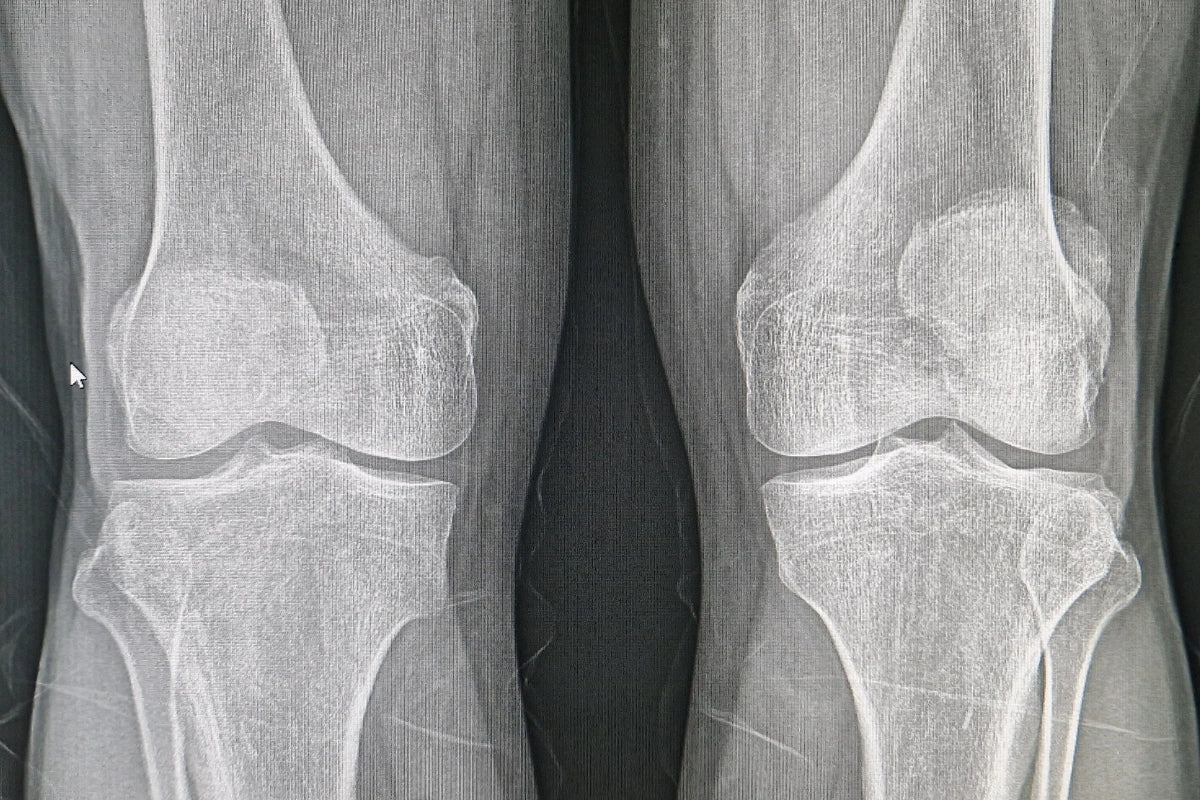

Mr. Maejima's bone density had risen from 2.71mmAI to an impressive 3.00mmAI—a dramatic increase of 10.7%. To put this in perspective, even NASA and JAXA astronauts who take Bisphosphonates in space to prevent bone loss typically see only a 1-5% improvement annually. And that comes at a cost: Bisphosphonates are known for their harsh side effects, including rare but severe conditions like atypical femur fractures and jaw osteoporosis.

Mr. Maejima applied the cream consistently as part of his treatment protocol. What followed was more than a slow recovery—it was a transformation. Not only did his bone density improve significantly, but his comfort, mobility, and outlook on life did as well.

For people like Mr. Maejima, and potentially millions more, the difference isn’t just on a chart—it’s in their everyday life. Being able to move without pain, walk confidently, and regain independence are priceless victories.